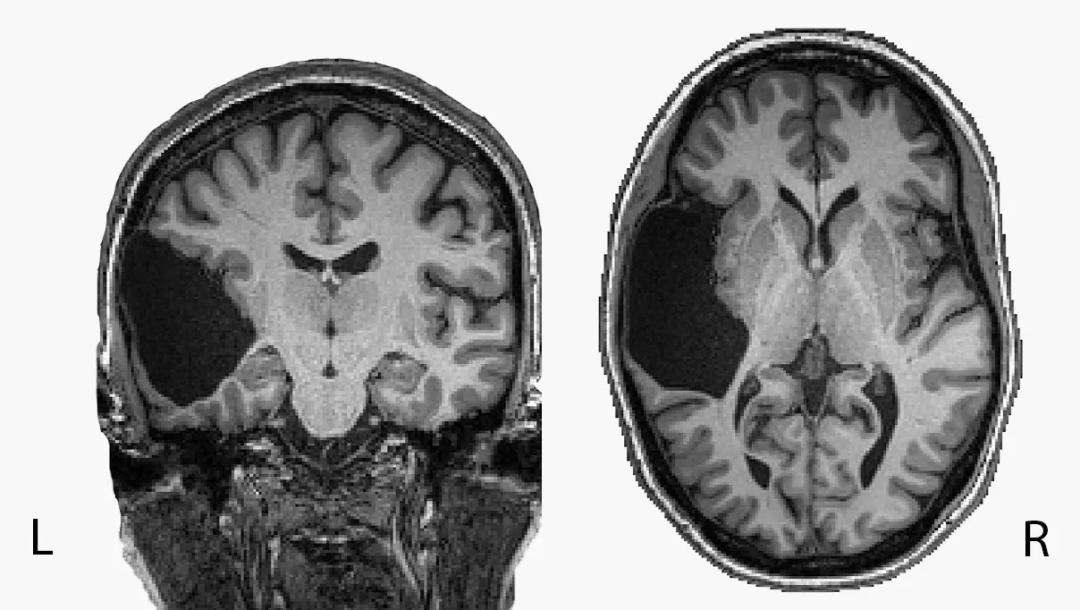

EG大脑的一幅核磁共振影像

EVELINA FEDORENKO, GRETA TUCKUTE/BRAIN AND COGNITIVE SCIENCES